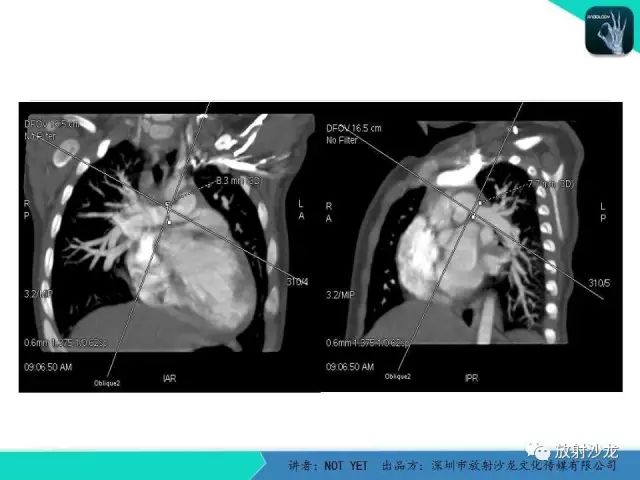

【病例】动脉导管未闭1例CT影像表现